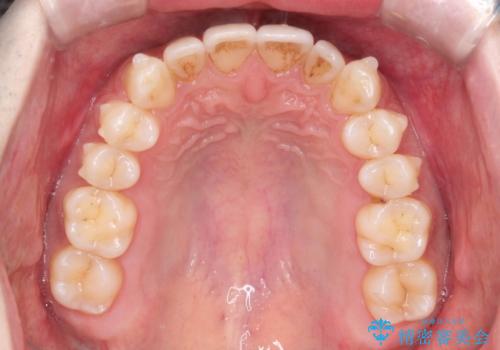

初診時の歯並びの状態としては、下顎に中等度のがたつき(叢生)がある状態でした。

抜歯は行わず下顎の奥のスペースを利用して歯をスライドする方法の他に親知らずの抜歯そして上下ともに歯列弓の拡大やディスキング(歯と歯の間の隙間を作る処置)を行い叢生を改善しました。

歯の大きさの不揃いが原因の正中のズレは、ディスキング量を調整することで合わせました。

矯正装置としてはマウスピースを使用しています。

見た目、嚙み合わせ及び、治療期間や施術内容に大変ご満足いただきました。